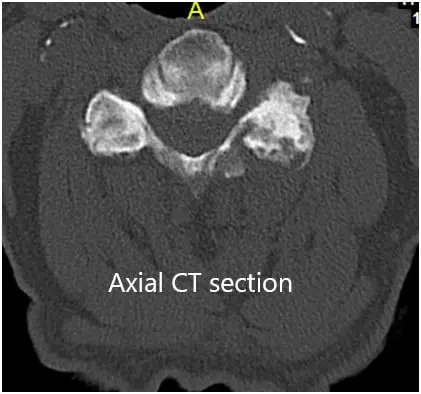

CT of the cervical spine demonstrated multilevel posterior disc bulges with bilateral neural foraminal stenosis of the mid to lower cervical spine. Sclerotic hypertrophic degenerative changes were associated with the mid to lower cervical facets.

Preoperative Coronal and Axial CT sections

Preoperative Coronal and Axial CT sections 2

Preoperative Coronal and Axial CT sections.